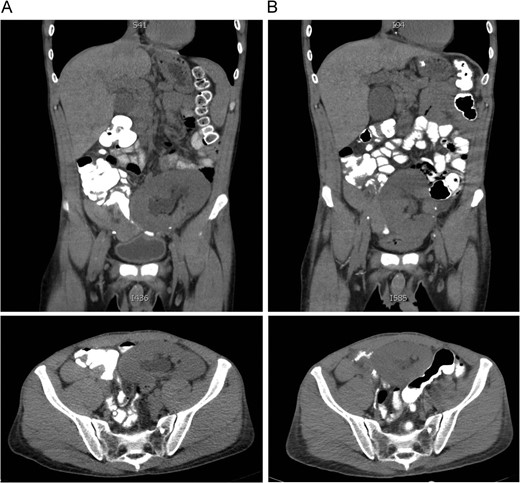

Comparison of CT scans obtained July 2015 (A) and August 2015 (B) showing migration of the transplanted renal allograft within the peritoneal cavity.

Presenting symptoms of nephroptosis most commonly include AKI, abdominal pain, decreased urine output and nausea/vomiting [3]. Doppler studies may reveal elevated flow velocities or complete occlusion of the vascular pedicle, but may also be normal if there is no active torsion of the renal allograft. Most common changes seen in a single study were shown to be reversed arterial diastolic flow, often with vascular thrombosis [1]. Identifying positional variations in renal blood flow may also be useful, although this has not been extensively studied. Sequential CT scans may also demonstrate migration of the renal allograft or change in axis, as was the case described above and has been reported previously as well [4].